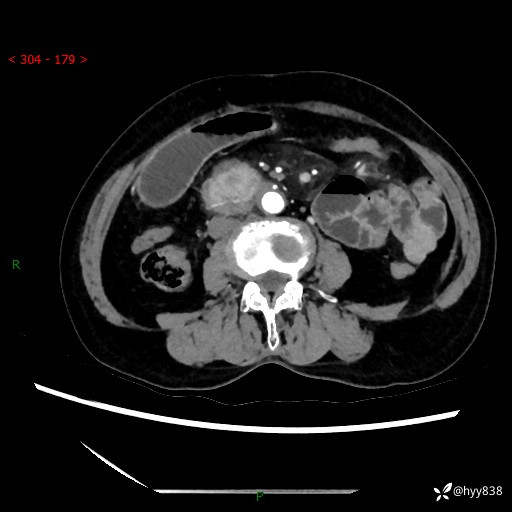

71岁/女,腹痛1月余。腹膜后肿物,间质瘤 VS 副节瘤 VS 平滑肌肉瘤---(有结果)

【患者信息】:71岁/女

【主诉】:腹痛1月余

【现病史及既往史】:患者于1月前无明显诱因出现右下腹部疼痛不适,呈阵发性隐痛,尚可耐受,放射至后背部及腰部疼痛,伴排便困难,不伴其它部位疼痛,无嗳气,无不洁饮食,无黑便,无恶心、呕吐、腹胀腹泻、呕血、发热、寒颤、厌油、黄疸,多次就诊于当地区太湖医院拍片示: 行抗炎等对症支持治疗,效果尚可。现患者上述不适症状明显进一步加重,为求进一步治疗遂来我院门诊就诊,门诊以“十二指肠肿瘤?”收住我科。 起病以来,精神、睡眠可,食欲可,大便异常、小便正常,体力、体重无明显下降。

【检查】:腹部CT增强扫描(外院CT平扫)